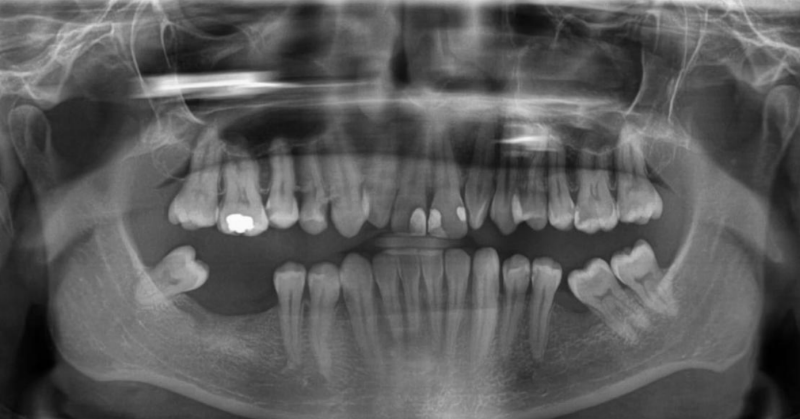

Hoe wordt een implantaatoperatie goed gepland? Het begint allemaal met een onderzoek ter plaatse en een röntgenfoto – dit is het eerste onderzoek dat algemene informatie geeft over het geval van de patiënt en de aan- of afwezigheid van voldoende kaakbot voor implantatie. Hier is een voorbeeld van een panorama(röntgen)foto:

Hoewel de röntgenfoto een goed hulpmiddel is om een algemeen beeld te krijgen van de situatie van de patiënt, is deze helaas niet voldoende voor een definitieve conclusie over de aanwezigheid van voldoende bot voor implantatie. De 3D-scan (CBCT) is echter een driedimensionaal röntgenonderzoek en vereist meer geavanceerde apparatuur. De kosten van de apparatuur zijn aanzienlijk en vaak wordt deze als externe dienst aangeboden, omdat niet elke kliniek zich dit kan veroorloven.